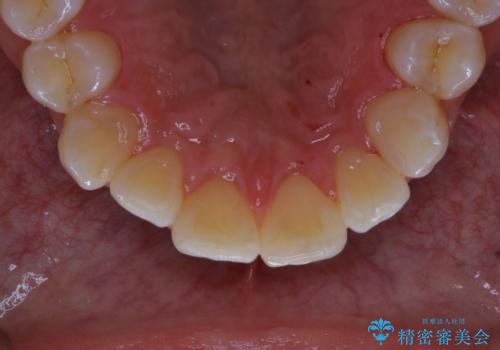

- 歯科でのクリーニングが5・6年ぶりで、全体をきれいにしたいとのことで来院されました。PMTC60分コースを行いました。

汚れを除去することにより、症状の早期発見につながります。

定期的に歯科医院に来院し、PMTCを行うことが大切です。

定期的にメンテナンスを行うことで、なにかあった時の早期発見につながります。